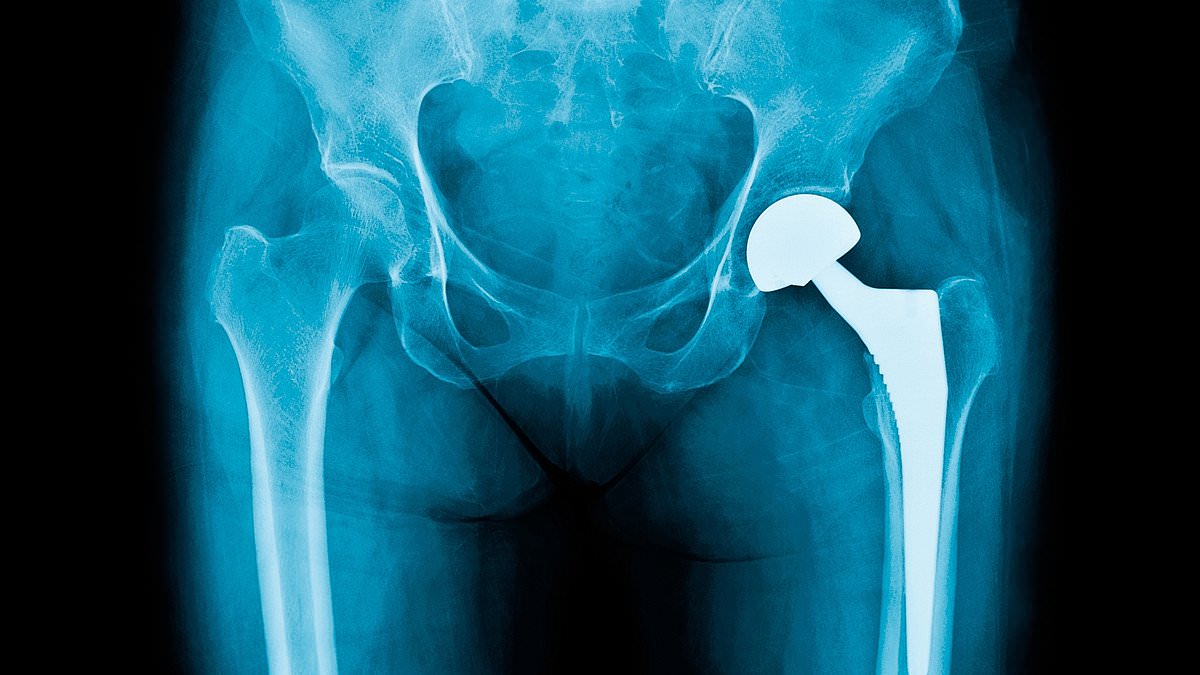

Bone cement, which is used to lock the replacement in place and get patients back to normal life quicker, is used in the majority of the 250,000 procedures carried out each year.

The crucial ingredient is thought to be used in more than 80 per cent of knee replacements and almost 60 per cent of hip replacements – which equates to around 15,000 operations every month.